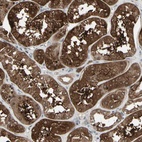

Immunohistochemical staining of human kidney shows strong cytoplasmic positivity in cells in tubules.